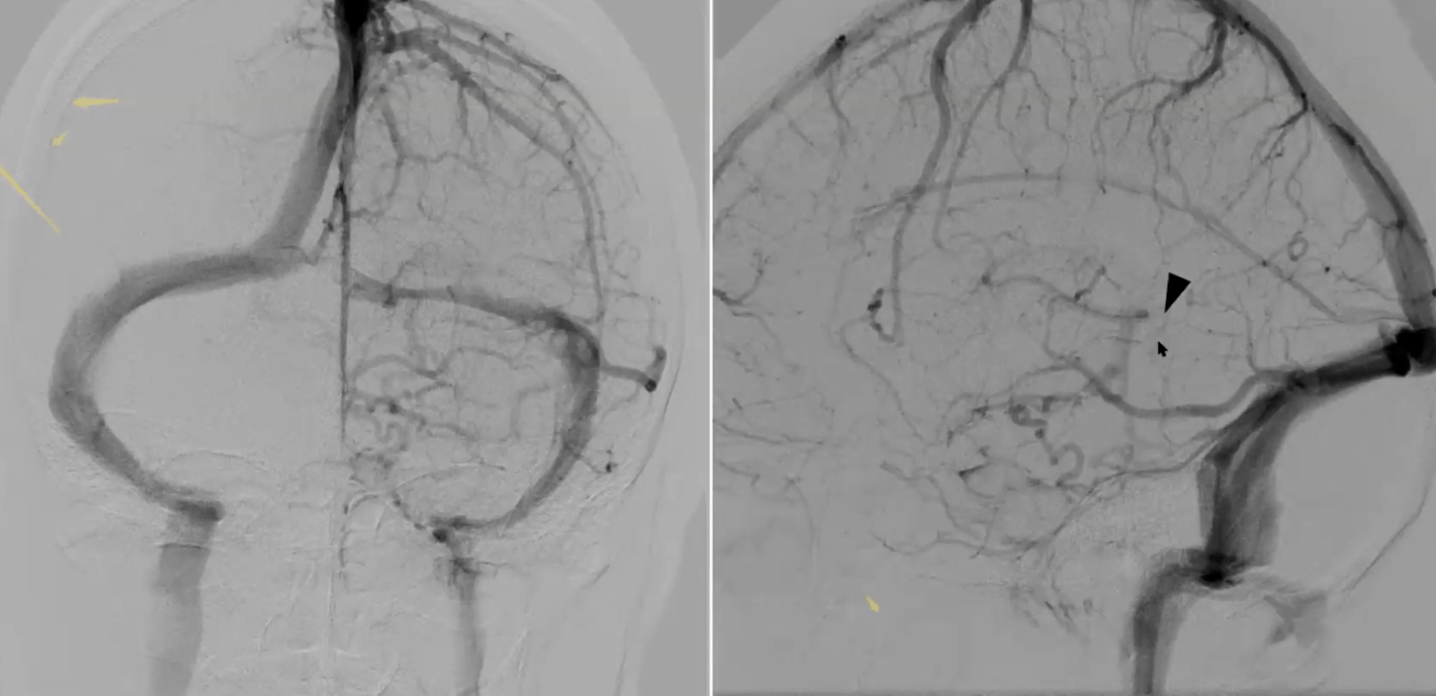

Pathologic early filling of this structure is seen on this AP view of the R CCA injection:

Cavernous sinus